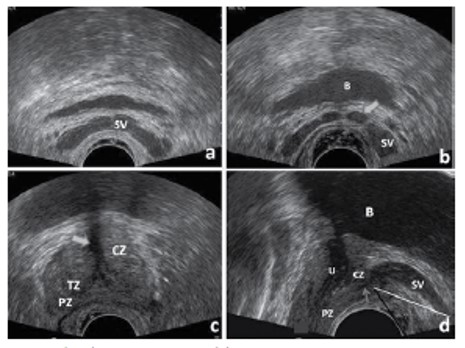

정상 전립선 소견. (a-c) transverse view, (d) sagittal view.

SV; seminal vesicle, CZ; central zone, TZ; transitional zone, PZ; peripheral zone,B; bladder, U; urethra

2. 경직장 초음파에서 정상 전립선 소견

• 전방섬유근구역은 대개 저에코로 보이고 이행구역도 요도 주위에서 저에코로 보인다.

• 중심구역과 주변구역은 초음파검사에서 에코는 유사하며 중등도에코를 보이거나 고에코를 보인다.

• 요도는 전립선 초음파에서 중요한 표지물(landmark)이 된다.

• 전립선 피막은 잘 구분되는 고에코 조직으로 관찰된다.

• 정낭과 정관은 얇은 벽을 가진 관상 구조물로 보인다. 정관의 팽대는 정낭과 합쳐저서 사정관을 형성한다.

• 정낭은 중앙부에서 좁아지는‘ beak sign’을 관찰할 수 있다. 일반적으로 정낭의 길이는 27-50 mm, 두께는 12-15 mm 정도 된다.